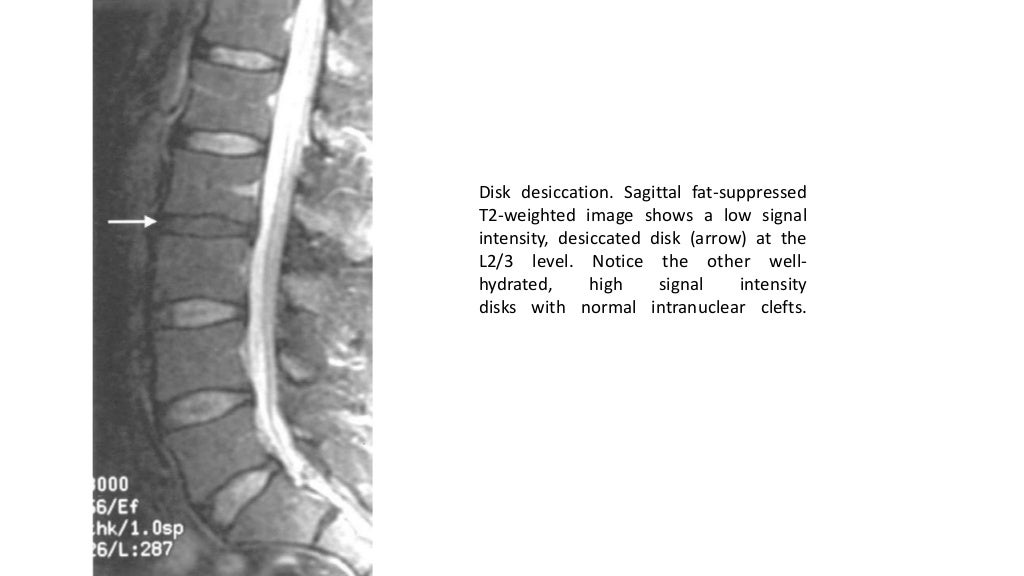

Imaging of lumbar spondylosis Is Lumbar Spondylosis Serious It can lead to pain, stiffness, and nerve compression in the neck and back, but most people are asymptomatic and don't need treatment. Spondylolysis most commonly affects your lower back (lumbar spine), but it can also happen in the other sections of your spine. Lumbar spondylosis and cervical spondylosis are the most common. Thoracic spondylosis frequently does not cause. While. Is Lumbar Spondylosis Serious.

Imaging of lumbar spondylosis Is Lumbar Spondylosis Serious Lumbar spondylosis and cervical spondylosis are the most common. Lumbar spondylosis can be described as a degeneration of the lumbar vertebrae. Spondylosis is a degenerative condition that affects the spine and causes arthritis in the joints and disks. Lumbar spondylosis refers to a degenerative condition affecting the lumbar spine resulting in chronic back pain and stiffness. Thoracic spondylosis frequently does. Is Lumbar Spondylosis Serious.